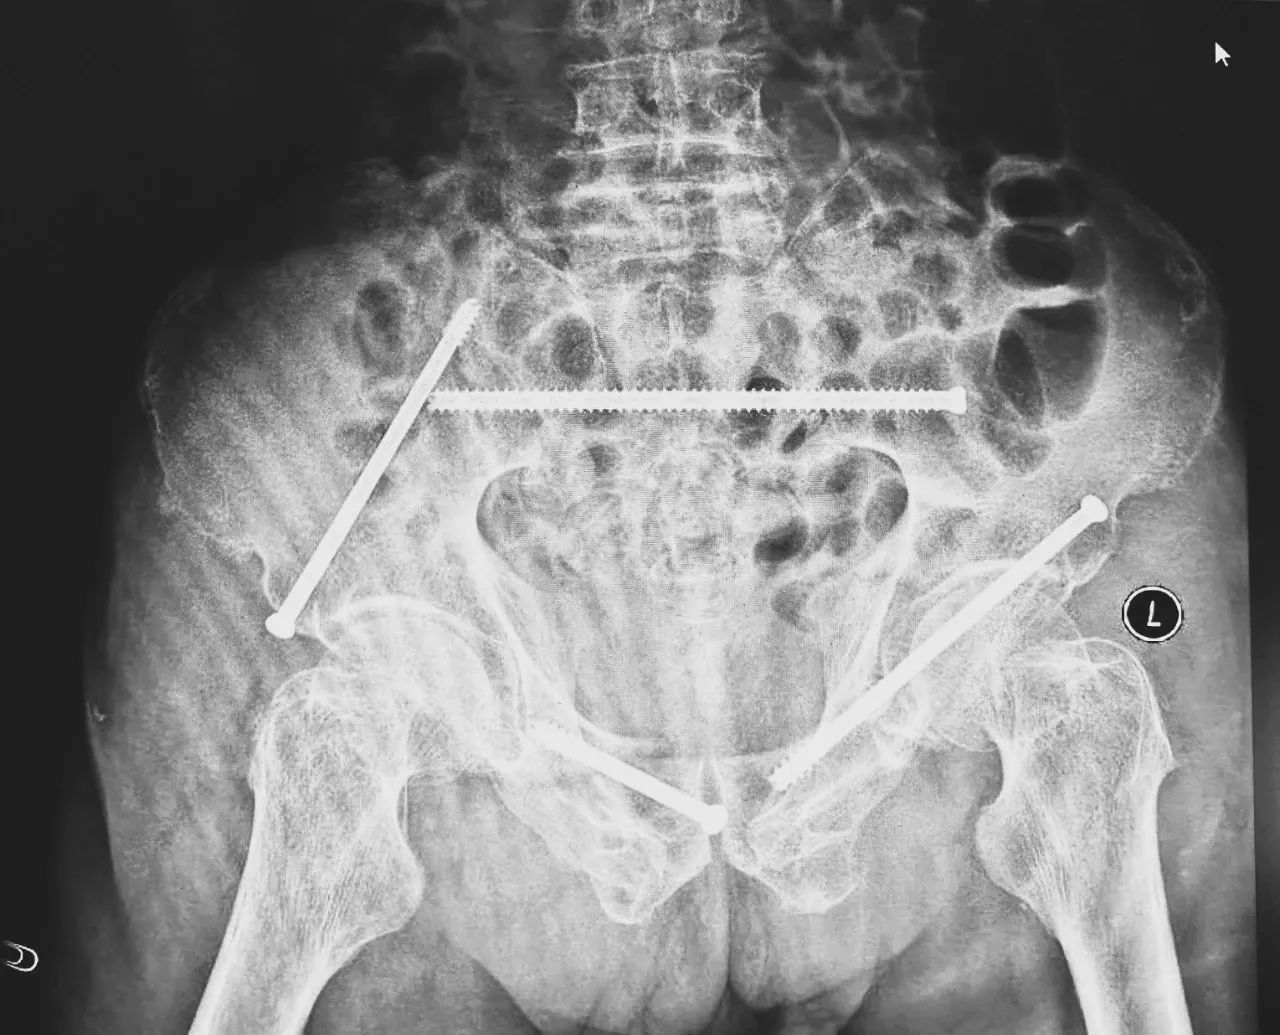

無影燈下,智能骨科團隊將患者示蹤器,放在左側(cè)髂前上棘,使用術(shù)中三維影像設(shè)備獲取骨盆的三維圖像,掃描結(jié)果傳輸至機器人導(dǎo)航系統(tǒng),完成螺釘置入的位置和走形,并在機器人的引導(dǎo)下分別置入4枚通道螺釘。置入后再次進(jìn)行CT掃描驗證,證實導(dǎo)針精確置入。

在骨科手術(shù)機器人毫米級精度的引導(dǎo)下,這項原本高難度、高風(fēng)險的手術(shù)變得更加精準(zhǔn)高效。手術(shù)共計耗時1個半小時,術(shù)中出血不到20毫升,每枚螺釘置入位置的切口長度約1.5厘米,完美達(dá)到了預(yù)期。術(shù)后,王大爺安全返回病房。

術(shù)后第二天,醫(yī)生團隊復(fù)查X片顯示螺釘植入位置非常滿意,骨折基本達(dá)到穩(wěn)定復(fù)位,同時,復(fù)查的全血細(xì)胞計數(shù)中,血紅蛋白指數(shù)為102g/L。術(shù)后第三天,在智能骨科病房護理團隊及康復(fù)師的指導(dǎo)和護理下,王大爺可以坐立在床上。術(shù)后第四天,王大爺迎來了出院日,“得虧有了這么先進(jìn)的醫(yī)療技術(shù),讓我還能下地行走,謝謝你們!”

螺釘植入位置非常滿意